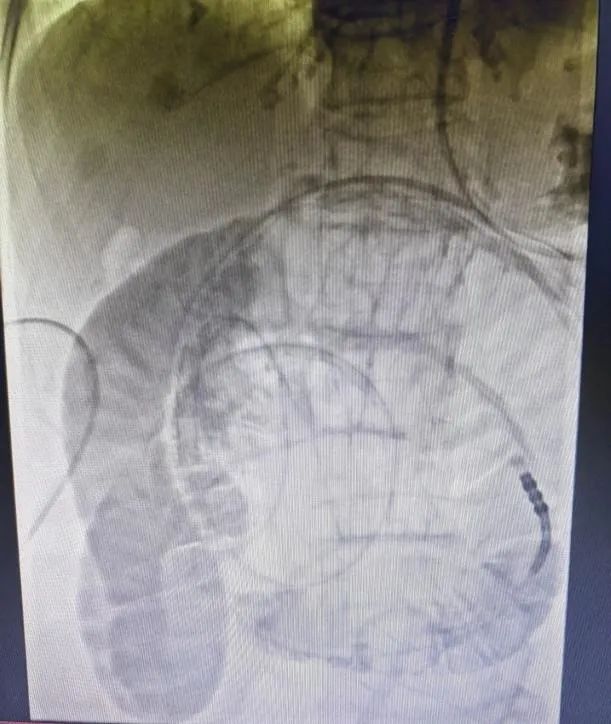

腸(cháng)梗阻導管置入時造影片

案例:患者,女,78歲,因“反複腹部脹痛伴肛門停止排(pái)氣排便3年”入院(yuàn),既往有闌尾切除術、輸尿管結石切開(kāi)取石術、輸卵管結紮術(shù)、鼻咽癌放療(liáo)史,有多(duō)次腸梗阻住院(yuàn)保守治療史,結合CT等(děng)檢查,診斷為粘連性腸梗阻,入院後禁食、解痙、抗感(gǎn)染、補液等對症支持(chí)治療(liáo)後,症狀未見明顯緩解,且腹脹逐漸加重,在(zài)DSA下消化道造影及腸梗阻導管置入,術後第二(èr)天梗阻緩解,肛(gāng)門排氣排便(biàn),從而進食,待腸道功能完全(quán)恢複後擇期行腹腔鏡(jìng)下腸粘連鬆(sōng)解術,術後6天(tiān)治愈(yù)出院。

腸梗阻是常見的外科急腹症之一,任(rèn)何原(yuán)因引起的腸內容物通過障礙統稱腸梗阻,其不但(dàn)可引起在腸管形態和功能上的改變,還可導致(zhì)一係列全身性病理生理改變(biàn),嚴重時可危及病(bìng)人(rén)的生命。腸梗阻的治療原則是糾正因腸梗阻所引起的全身生理紊亂和解除梗阻,包括手術治(zhì)療和非手術治療,其中胃腸減壓為(wéi)非手術治療的主要措施之一,傳統的(de)胃腸減(jiǎn)壓(yā)管隻能(néng)放到胃,減(jiǎn)壓效果不夠理想及迅速;而腸梗阻導管是在DSA下通(tōng)過造影判斷解剖及位置,利用導絲、導管技術將減壓管放入小腸,同時通過導管前端水囊的重力及腸蠕動(dòng)作用,將導管推致(zhì)梗阻(zǔ)部(bù)位或者更遠端,從而可快速、精準解(jiě)除梗阻、緩(huǎn)解症狀。同時此技術(shù)的運(yùn)用可避免梗阻不能緩解尤其是粘連性腸梗阻患者的急診手術,通過導管解壓,促進腸道通暢及功(gōng)能恢複,從而擇期選擇腹腔鏡或開放手術解除梗(gěng)阻原因,進一步降低手術風險及並發症的發生,從而達到(dào)縮短住院時間(jiān)及減少創(chuàng)傷的效果。武寧縣人民醫院普外(wài)科已開展DSA下腸梗阻導管置入術,且取得較好療效。